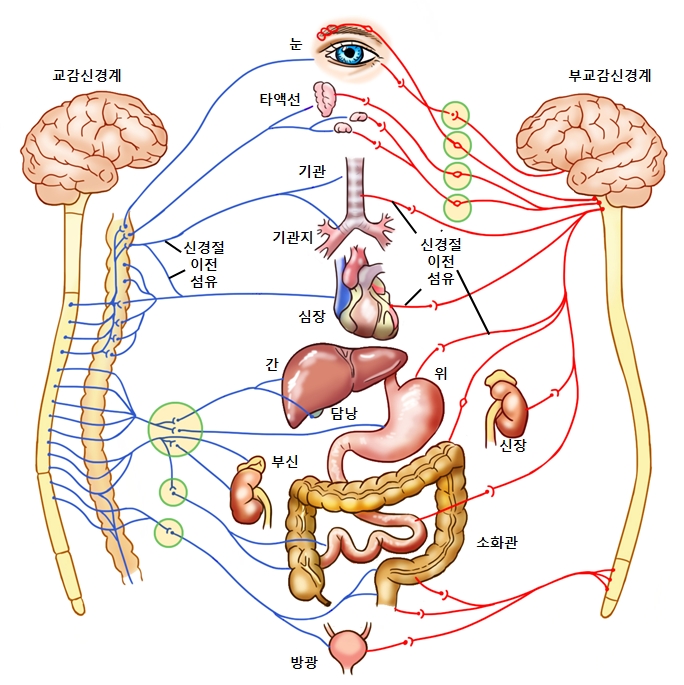

자율신경계

교감신경과 부교감신경으로 나눌 수 있습니다. 이들은 서로 반대작용을 합니다.

교감 신경

척수의 중간 부분에서 나와 여러 내장기관에 분포합니다.

부교감 신경

중뇌와 연수 및 척수의 꼬리부분에서 나와 여러 내장기관에 분포합니다.

자율신경계는 뇌의 명령을 받지 않아도 독립적으로 움직이며 상황에 맞추어 체내 항상성을 유지합니다. 자율신경계의 지배를 받고 있는 내분비, 폐, 호흡 등은 우리의 의사로 조절할 수 없습니다.

교감신경

교감신경은 위급한 상황에 빠졌을 경우 빠르게 대처할 수 있도록 도와줍니다. 교감신경 자극 시 골격과 신경으로가는 혈액양이 늘어나며 심장박동은 빨라지고 감각도 예민해집니다.

부교감신경

부교감신경은 위급한 상황에 대비하여 에너지를 저장해두는 일을 합니다. 부교감 신경 자극 시 내장으로 가는 혈액양은 늘어나 소화, 배설이 활발해지고 심장박동이 느려져 에너지 사용이 줄어들게 됩니다.